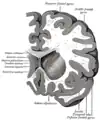

Transverse cut of brain (horizontal section), basal ganglia is blue | |